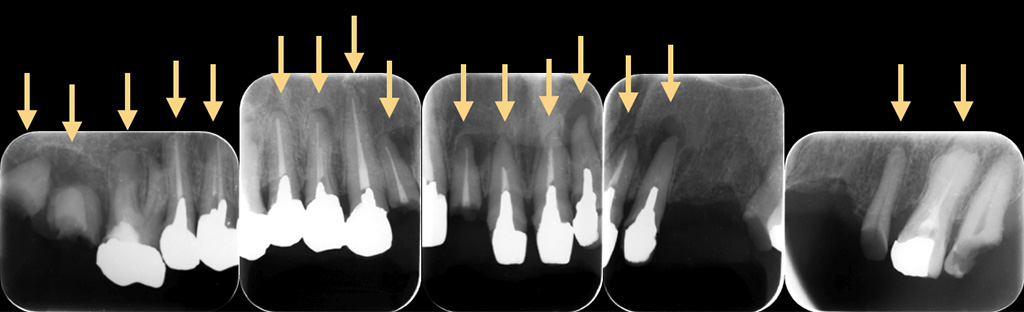

上記のようにいくつかのパターンがあります。ゆっくり大きくなると無症状に進行し、気がつくと隣の歯に病巣が到達してしまった、ということも少なくありません。このようなことを聞くと皆様「怖い」と思われる方もいらっしゃいますが、根尖性歯周炎は決して少なくありません。私の経験では、むしろ非常によく出くわします。(図4)

図4

ある患者様の上の歯のX線写真。ほとんどの歯がすでに根管治療がされているが、全ての歯が根尖性歯周炎になっている。